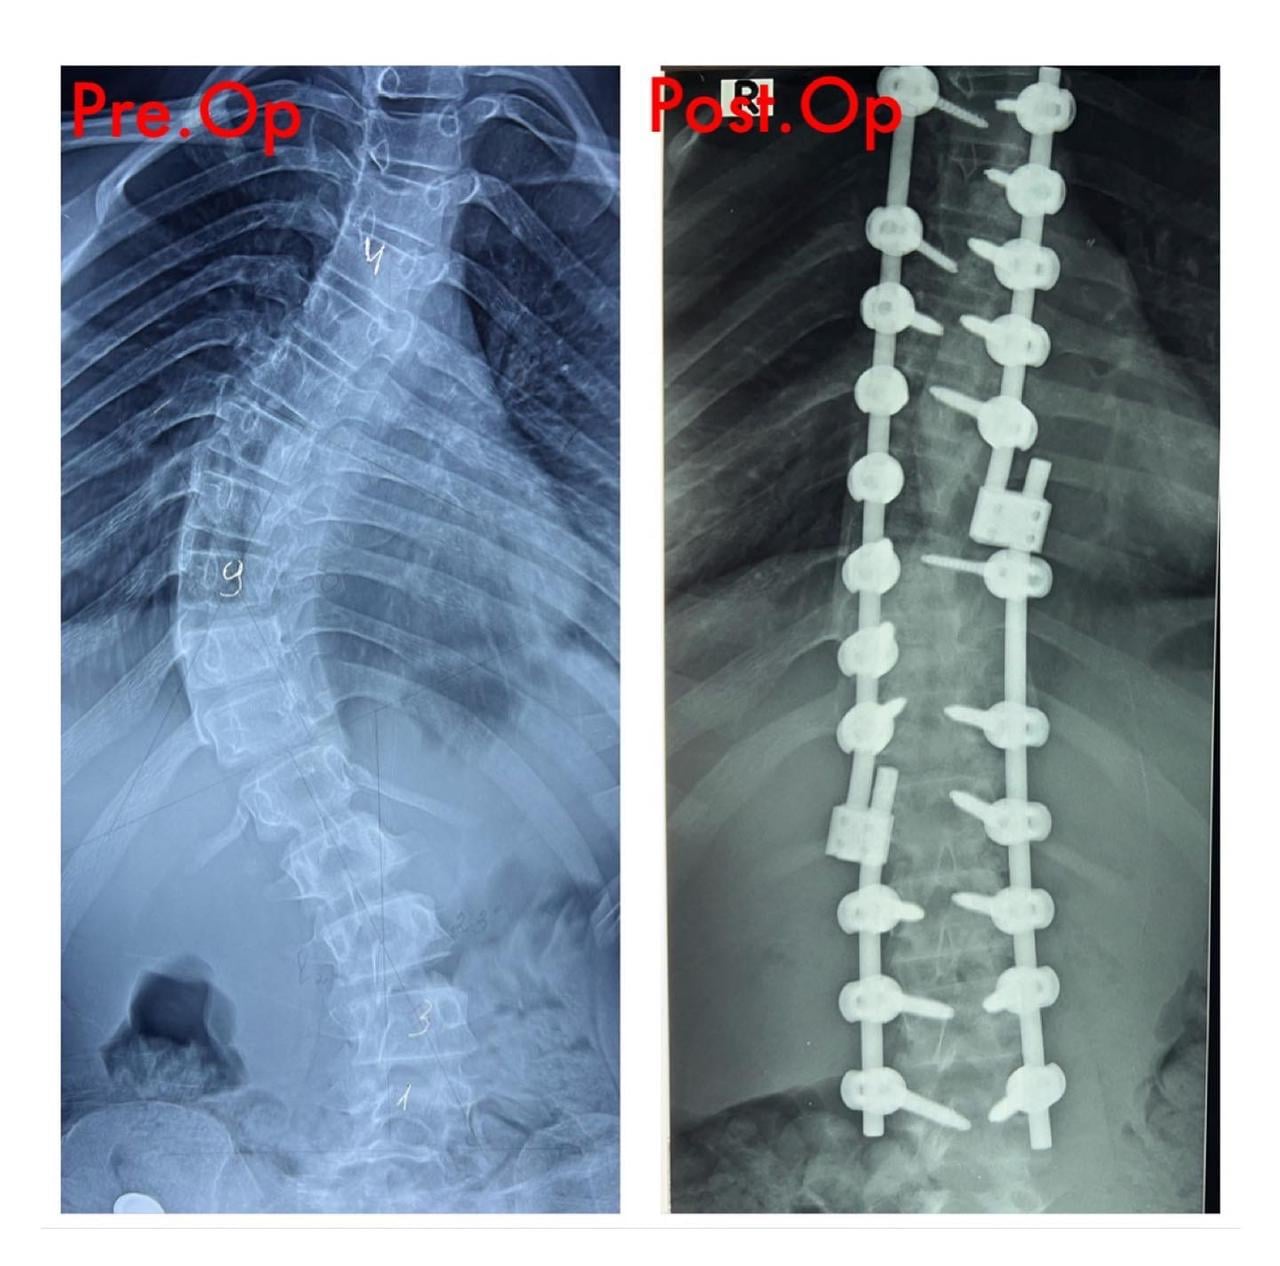

Azərbaycan Tibb Universitetinin Tədris Cərrahiyyə Klinikasında skolioz diaqnozu qoyulmuş 12 yaşlı uşaq cərrahi əməliyyat olunub. Əməliyyat klinkanın Neyrocərrahiyyə şöbəsinin assistenti Cəmil İskəndərovun rəhbərliyi ilə həyata keçirilib.

Aztibb.az xəbər verir ki, neyrocərrahın bildirdiyinə görə, uşaqda skolioz xəstəliyi 10 yaşında aşkar olunub: “Xəstə son dövrlər korsetdən istifadə etməsinə baxmayaraq, onda sürətlə əyilmə prosesinin getməsi müşahidə edilirdi. Əyilmə 45 dərəcədən artıq idi. Prosesin qarşısını almaq mümkün olmadığı üçün onu əməliyyat etməyi qərara aldıq. Sevindirici haldır ki, əməliyyat uğurlu həyata keçdi. Artıq ertəsi gün xəstə gəzdirildi. Vəziyyəti qənaətbəxş olduğu üçün 4 gündən sonra evə yazıldı. O, hazırda özünü normal hiss edir”.

Həkim ağır əməliyyat olmasına baxmayaraq uşağın onurğasının tez bir zamanda bərpa olunacağına, normal həyata dönəcəyinə və təhsilini davam etdirəcəyini diqqətə çatdırıb.